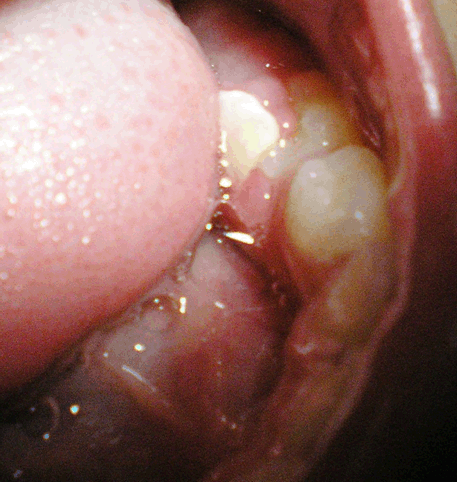

Intraoral examination revealed a primary dentition. All the primary teeth were present. A tooth-like structure was observed in the gingival tissue overlying the lower left second deciduous molar. It was situated lingually and appeared to overlap the linguo-occlusal aspect of the crown of the deciduous mandibular left second molar. The deciduous mandibular left second molar was slightly below the plane of occlusion. The surrounding mucosa showed signs of inflammation (Figure 1).

Cursor on image to zoom/Click text to open image

Figure 1: Clinical presentation of the case.